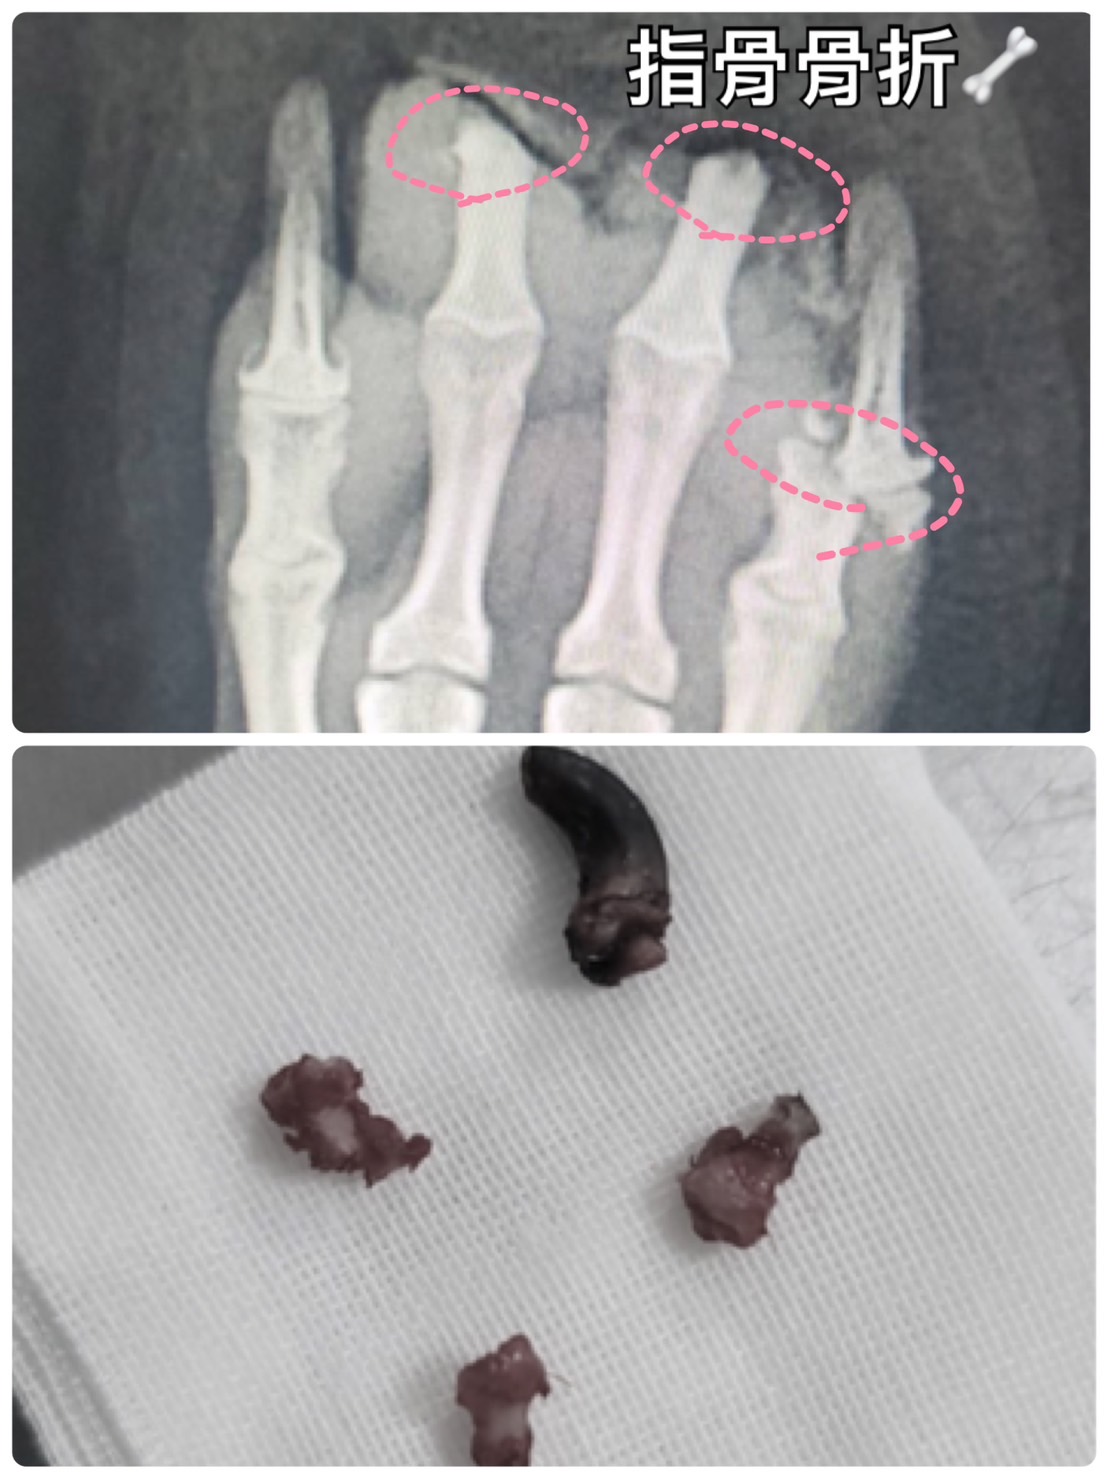

創傷骨科疾病

指骨骨折、創傷

#第三至五指骨骨折

住院期間進行

#清創截指

#重建手術

#傷口雷射護理

復原後外觀和功能完全正常